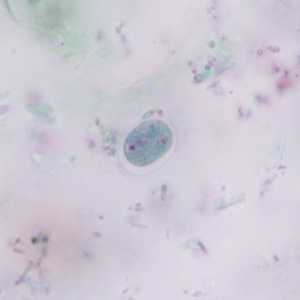

E. polecki cysts stained with trichrome.

Figure A: Cyst of E. polecki stained with trichrome. Notice the large nucleus with a pleomorphic karyosome and numerous variably-shaped chromatoid bodies.

Figure B: Cyst of E. polecki stained with trichrome. Notice the large nucleus with a pleomorphic karyosome and numerous variably-shaped chromatoid bodies.

Figure C: Cyst of E. polecki stained with trichrome. Notice the large nucleus with a pleomorphic karyosome and numerous variably-shaped chromatoid bodies.

Figure D: Cyst of E. polecki stained with trichrome. Notice the large nucleus with a pleomorphic karyosome and numerous variably-shaped chromatoid bodies.

Figure E: Cyst of E. polecki stained with trichrome. Notice the large nucleus with a pleomorphic karyosome and numerous variably-shaped chromatoid bodies.

Figure F: Cyst of E. polecki stained with trichrome. Notice the large nucleus with a pleomorphic karyosome and numerous variably-shaped chromatoid bodies.